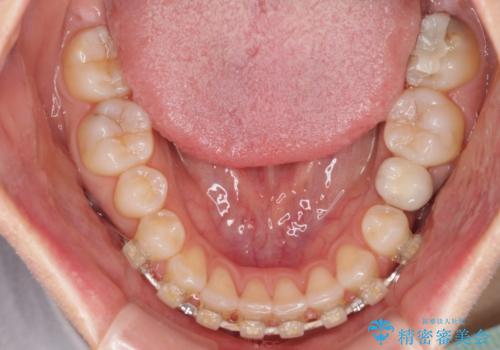

下顎前歯は空隙歯列弓であったので、アンカースクリューとワイヤー装置を用いてスペースを閉じていくこととし、上顎前歯は矯正治療用の仮歯に置き換えた上で、仮歯の大きさを削って小さくしながら、上下前歯部の部分矯正を行うこととしました。

日本と海外を拠点に仕事をされていらっしゃるため、数ヶ月治療があいてしまうことがあり、期間はかかりましたが、2年間で望み通りの前歯に仕上げることができました。